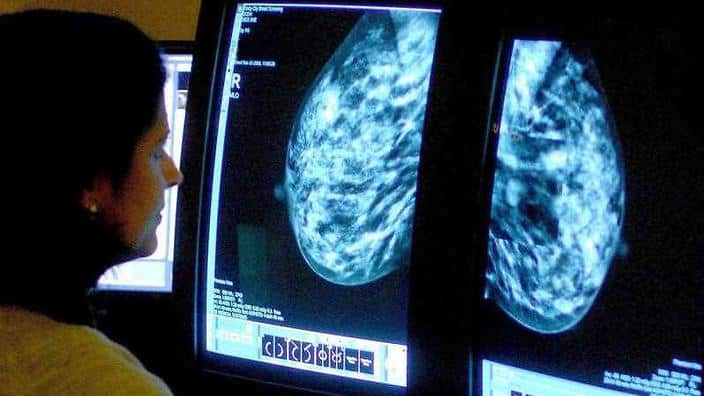

කුකුළු මස් සහ පියයුරු පිළිකා

පිළිකා පිළිබඳ ජාත්යන්තර ජර්නලයේ අගෝස්තු මස ප්රකාශනයේ අවධානය යොමුව තිබුණේ රතු මස් සහ කුකුළු මස් ආහාරයට ගැනීම හා පියයුරු පිළිකා අතර ඇති සම්බන්ධය පිළිබඳ තොරතුරු අනාවරණය කරගැනීමටය.

රතු මස් ආහාරයට ගන්නා කාන්තාවන්ට වඩා කුකුළු මස් ආහාරයට ගන්නා කාන්තාවන්ට පියයුරු පිළිකා ඇතිවීමේ අවදානම අඩු බව එහිදී හෙළිවී තිබේ.